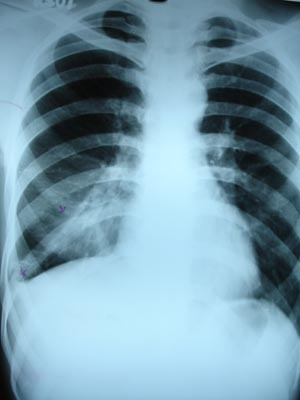

Minimal pleural effusion2